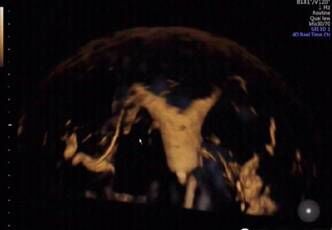

——三维输卵管超声造影技术

我院超声医学影像科最新引进了美国GEVolusonE8彩色多普勒超声仪和超声造影剂六氟化硫微泡(声诺维),可以用于三维/四维子宫输卵管超声造影检查。 超声输卵管造影术是通过向宫腔注入造影剂后,使原本闭合的宫腔和输卵管扩张,然后进行三维成像,主要用于评价输卵管通畅性和诊断子宫宫腔病变。由于子宫输卵管超声造影和三维超声的完美结合,超声声像图的质量得到明显改善,并可获得更多的信息,使诊断的敏感性和特异性显著提高。

三维/四维超声输卵管造影,能够快速、准确地评估输卵管的通畅性,是筛查输卵管通畅性的有效手段